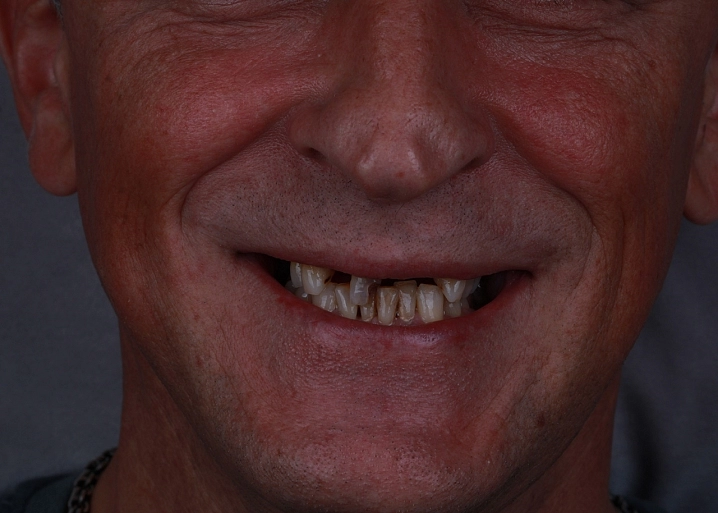

Проведена полная эстетическая реставрация зубных рядов верхней и нижней челюстей винирами E-max. Восстановлена форма, размер, цвет и поверхность фронтальных зубов, достигнута гармоничная улыбка.

Проведена эстетическая реставрация передних зубов верхней и нижней челюстей винирами E-max. Исправлены форма, размер и восстановлена поверхность зубов.

Пациент прошел комплексную диагностику и 3D моделирование улыбки. После этого были изготовлены и установлены керамические виниры E-max, что позволило добиться гармоничного и естественного вида зубов.